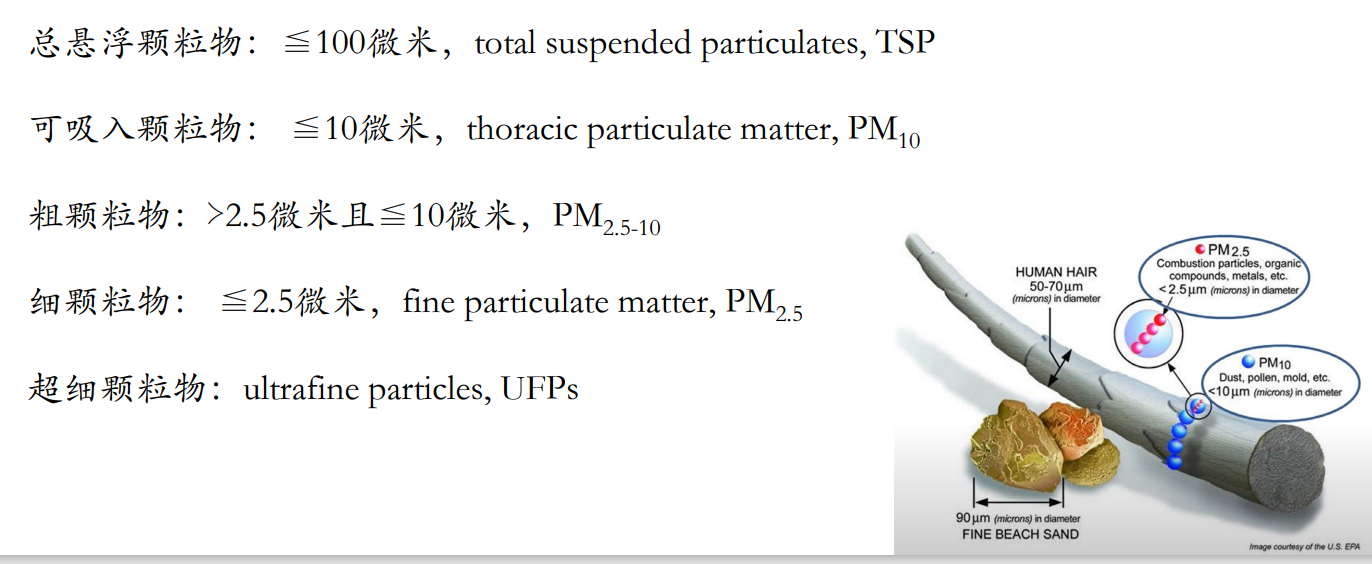

PM(Particulate Matter)

PM2.5 是指直径小于或等于2.5微米的颗粒物,是由直接排入空气中的微粒和空气中的气态污染物通过化学转化生成的二次微粒共同组成。

颗粒10 µm 时,沉积在上呼吸道。颗粒在5 µm时,可进入呼吸道的深部。颗粒小于2 µm时,深入到细支气管和肺泡。

颗粒大于5 µm 时,侵袭在鼻腔和上呼吸道中。引起鼻炎,咽炎,喉炎。

颗粒在3-5 µm时,侵袭到细支气管。引起支气管炎,支气管扩张,肺炎,哮喘等疾病。

颗粒小于1-2 µm时,侵袭到肺泡。引起肺气肿、肺癌、肺纤维化等疾病